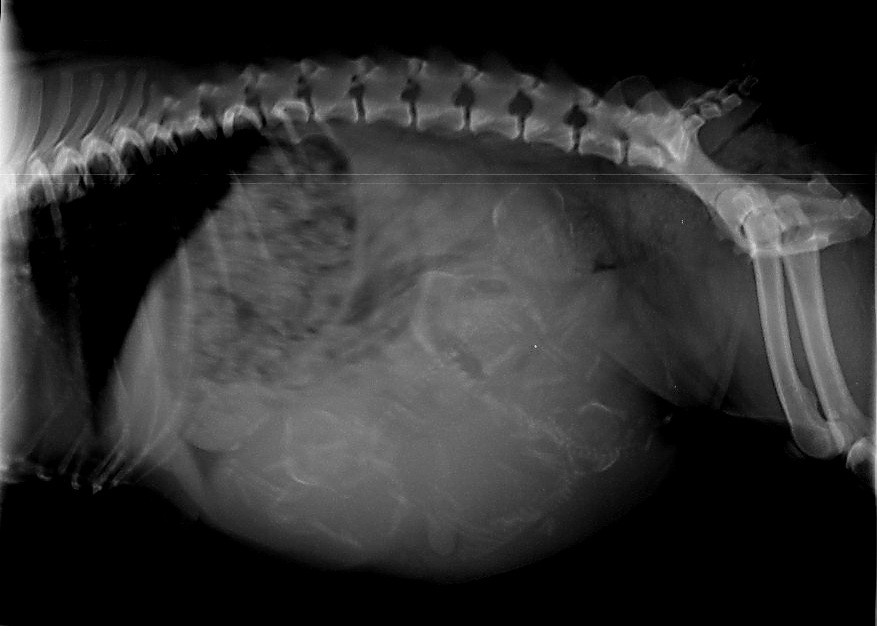

Ich habe einen Luftballon verschluckt. Hilfeeeeee.....       Am 60.Tag .....

Ich habe schwer zu tragen. Hier am 58. Trächtigkeitstag

Der 58. Tag der Trächtigkeit